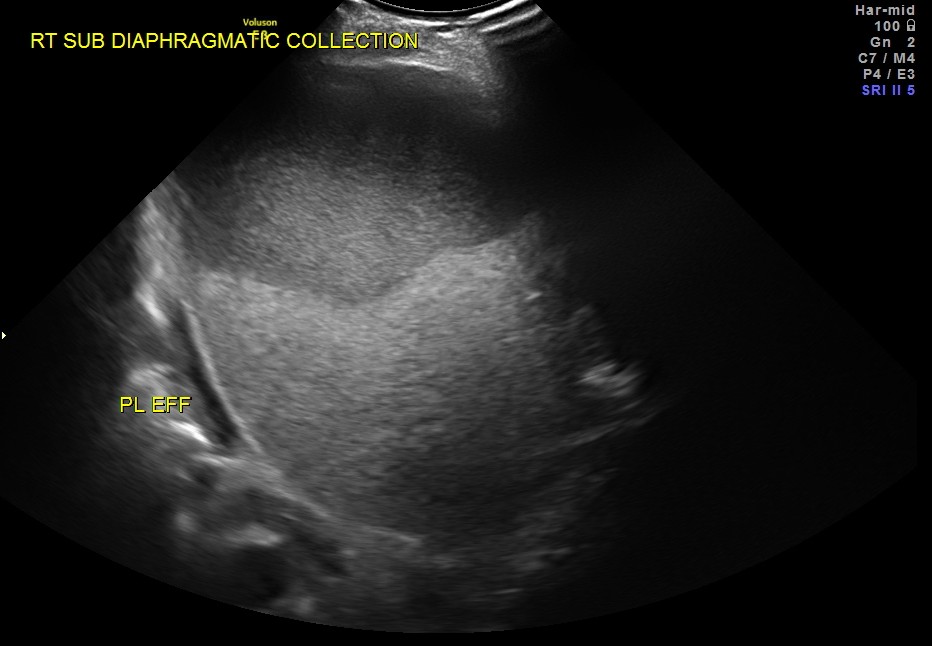

SUB DIAPHRAGMATIC COLLECTION , PROBABLY LOCULATED WAS ALSO SEEN. MINIMAL RIGHT PLEURAL EFFUSION WAS ALSO SEEN.